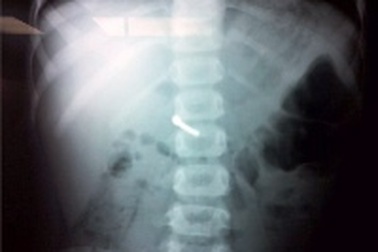

Còi đồ chơi chui tọt vào phế quản bé trai 3 tuổiKhi đang ngậm kèn nhựa để thổi, bé N. M.Q. (3 tuổi, Sóc Sơn, Hà Nội) ho sặc sụa, phần còi của chiếc kèn chui tọt vào miệng bé.

Tiếng kèn rít “te… te” trong phổi bệnh nhi 3 tuổiSau nhiều tháng ho, khò khè và tức ngực, dù đã điều trị đủ mọi phương thuốc nhưng không thuyên giảm. Tại bệnh viện Nhi Đồng 2, qua ống nghe bác sĩ phát hiện phổi của bé có tiếng rít “te… te” như tiếng kèn thổi.